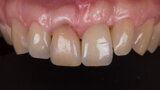

Immediate placement and restoration of a Straumann BLX implant replacing maxillary incisors